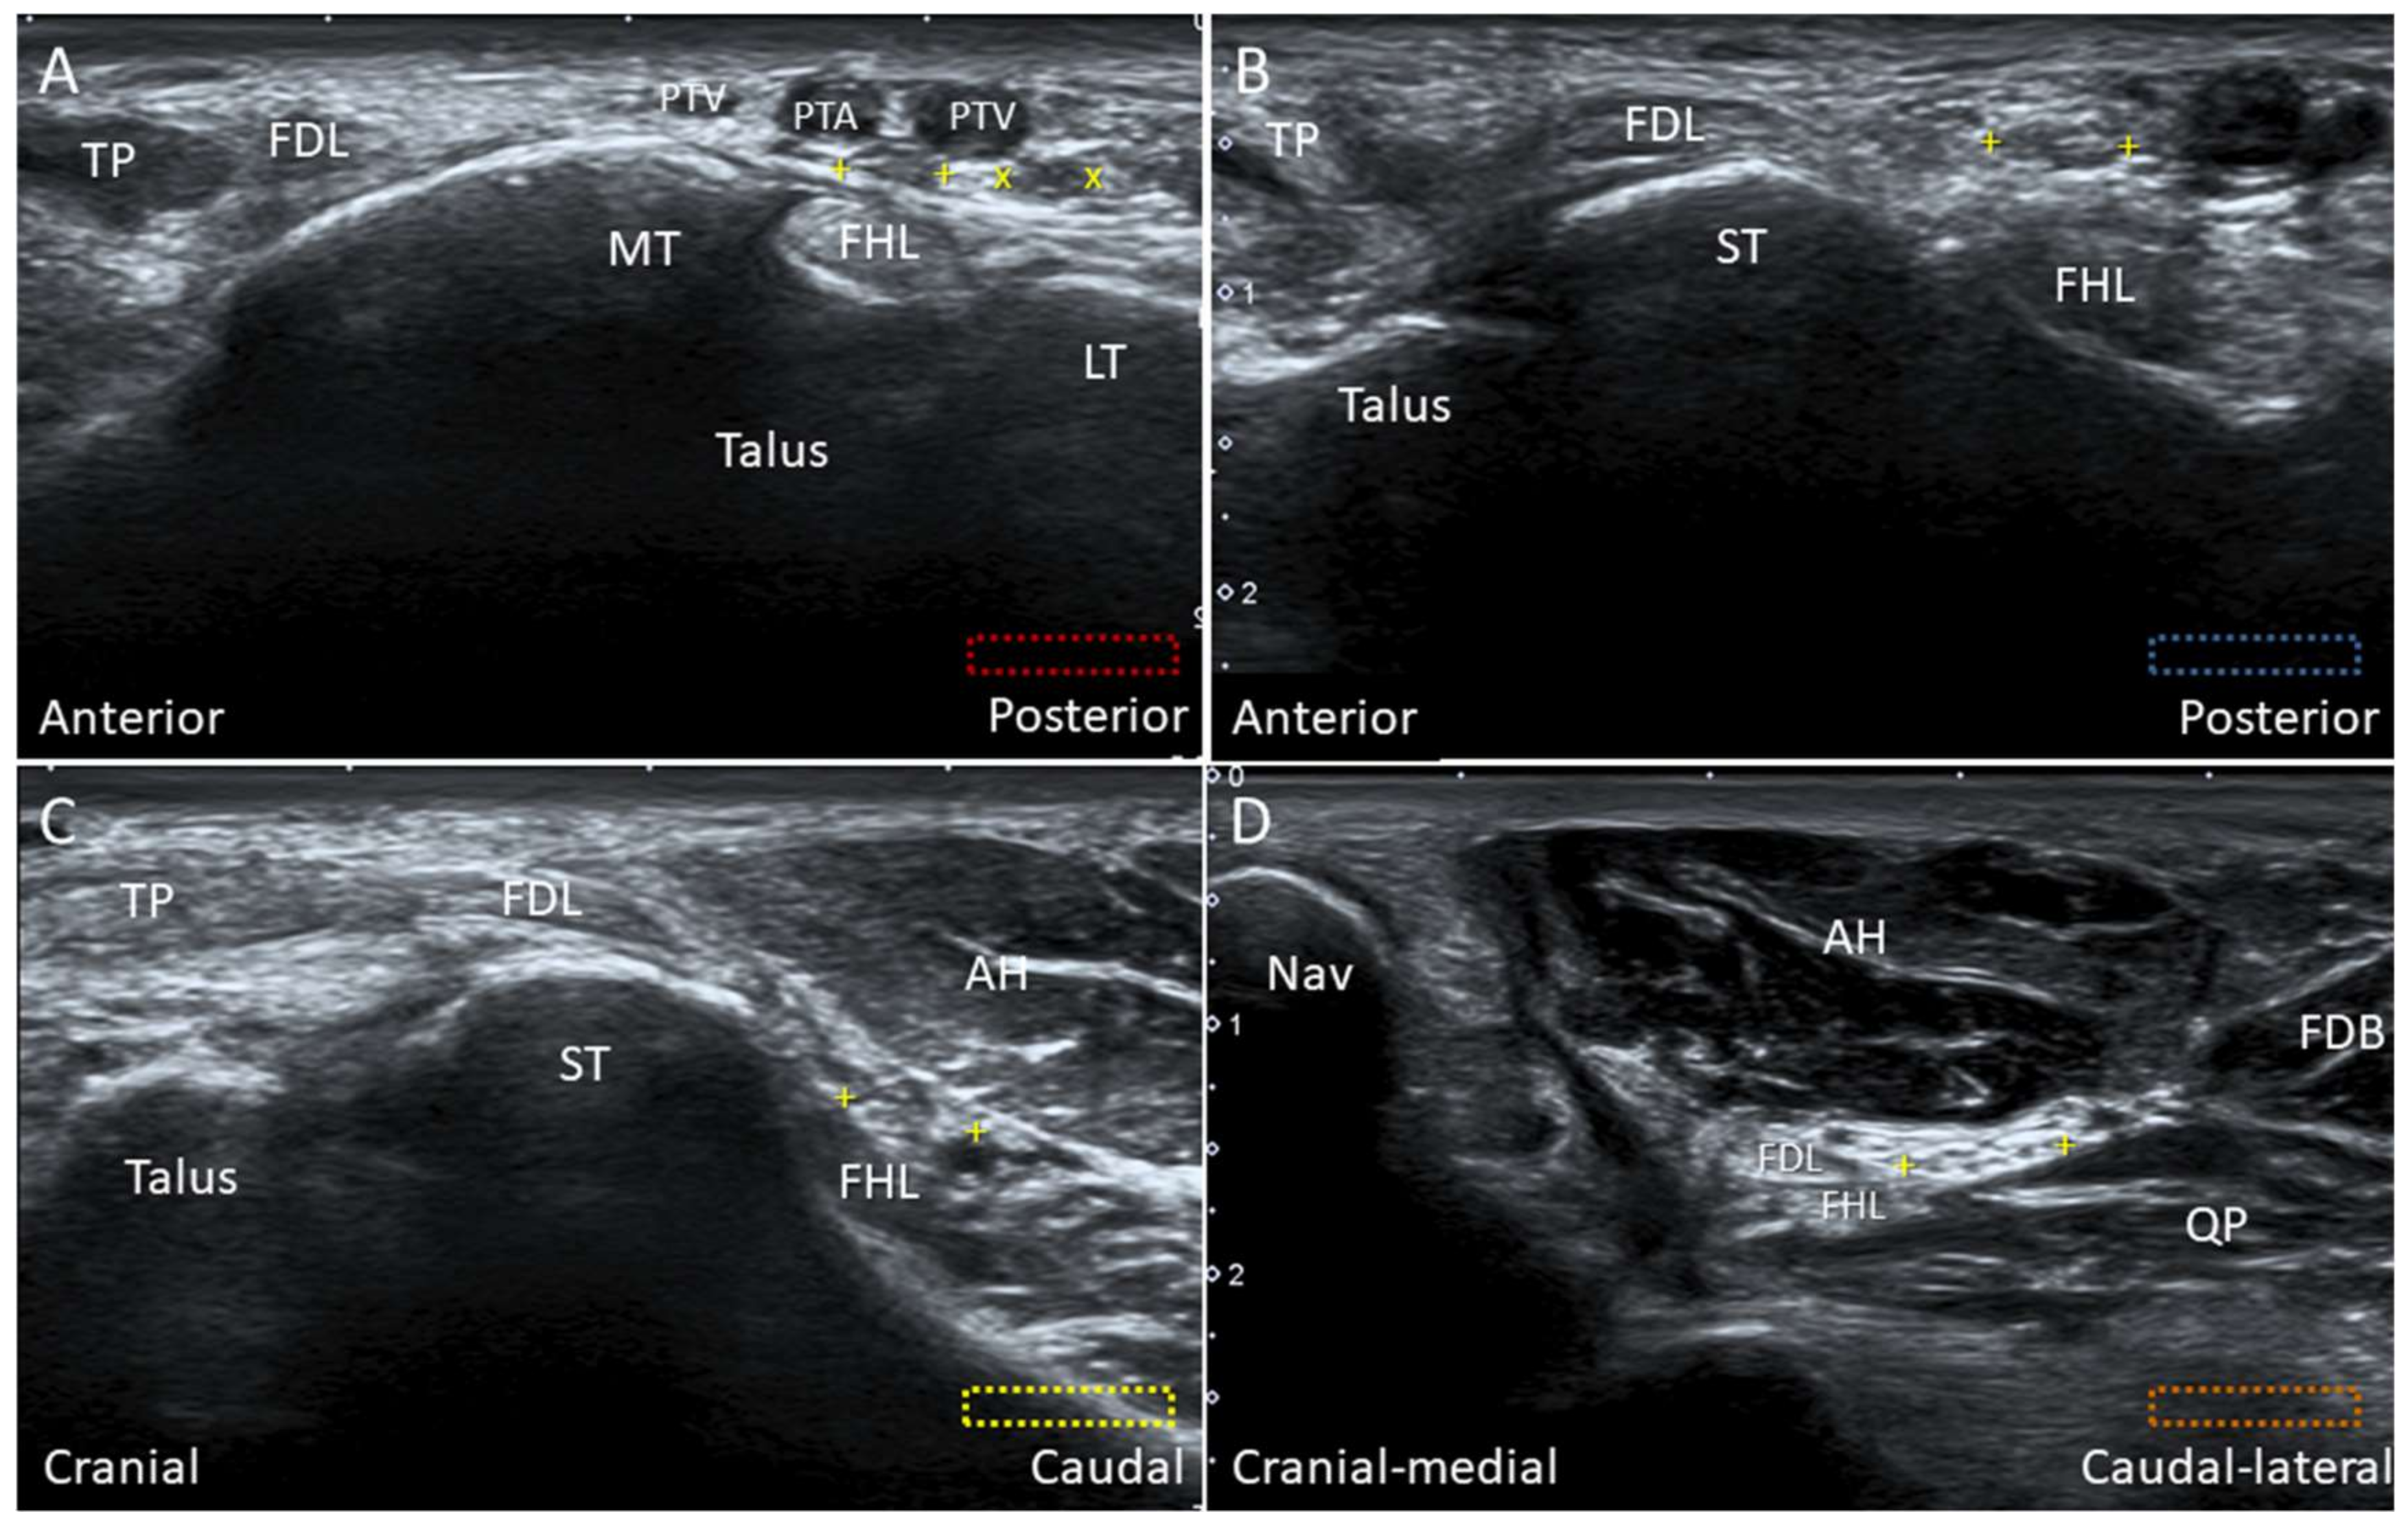

5.1. Medial Plantar Nerve (Over the Knot of Henry)

5.1.1. Anatomy

5.1.2. Scanning Technique

5.1.3. Clinical Relevance

5.2. Baxter Nerve

5.2.1. Anatomy

5.2.2. Scanning Technique

5.2.3. Clinical Relevance